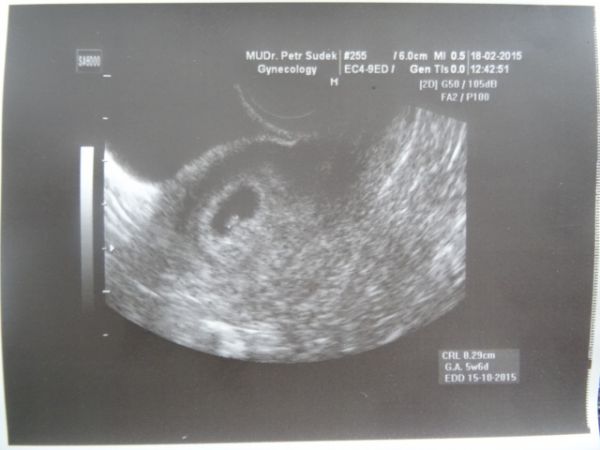

Ahoj :a: tak se Vám představuji. TP mi vychází dle UTZ na 15.10.2015, doufám že jsem :girl: Terezka. Zatím jsem veliká 3mm, ale srdíčko mi už bije :h: zdravím kamarádi a kamarádky